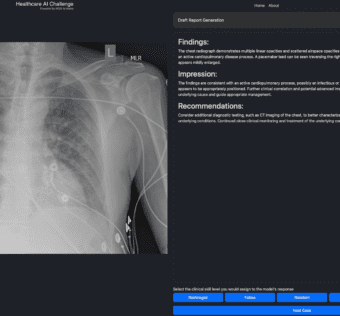

Mass General Brigham Launches Healthcare AI ChallengeHIT Consultant - (Wednesday November 13, 2024) - AI/ Digital Health/ Frequent Updates/ HIT Consultant | |

![]() | What You Should Know: – Mass General Brigham AI is spearheading the Healthcare AI Challenge, a multi-institutional initiative designed to assess the latest AI technologies in real-world healthcare scenarios. – The virtual, interactive series of events... Mass General Brigham is launching the Healthcare AI Challenge, a collaborative initiative aimed at evaluating AI technologies in real-world healthcare settings. This virtual series enables healthcare professionals to assess AI solutions through interactive challenges, fostering innovation and responsible adoption. By crowdsourcing expertise, participants will provide insights on AI performance, enhancing transparency and informed decision-making. The challenge will continuously evolve, incorporating new solutions and specialties to keep pace with rapid AI advancements. As Keith Dreyer states, this initiative empowers clinicians to evaluate AI's utility, ultimately advancing patient care.#HealthcareAI #HealthTech #AIinHealthcare #Innovation #PatientCare #Collaboration #DataScience As a healthcare IT expert, write a 100-word extractive summarization based on a blog post from the given text for posting on LinkedIn. The summary should capture key ideas from the entire post and its headings while staying focused, clear, and engaging. Use 5-7 relevant and popular online hashtags that are most likely to drive visibility and engagement. Avoid adding URLs or calls to action, and ensure the language is optimized for LinkedIn engagement style with a variable potential hook or attention-grabbing statement. The target audience is other healthcare IT professionals. Following is the title and text. { "id": "chatcmpl-ATCdlVLWdqlzFc1F6uUaKAvOUR3c1", "object": "chat.completion", "created": 1731523465, "model": "gpt-4o-mini-2024-07-18", "choices": [ { "index": 0, "message": { "role": "assistant", "content": "Mass General Brigham is launching the Healthcare AI Challenge, a collaborative initiative aimed at evaluating AI technologies in real-world healthcare settings. This virtual series enables healthcare professionals to assess AI solutions through interactive challenges, fostering innovation and responsible adoption. By crowdsourcing expertise, participants will provide insights on AI performance, enhancing transparency and informed decision-making. The challenge will continuously evolve, incorporating new solutions and specialties to keep pace with rapid AI advancements. As Keith Dreyer states, this initiative empowers clinicians to evaluate AI's utility, ultimately advancing patient care. nn#HealthcareAI #HealthTech #AIinHealthcare #Innovation #PatientCare #Collaboration #DataScience", "refusal": null }, "logprobs": null, "finish_reason": "stop" } ], "usage": { "prompt_tokens": 791, "completion_tokens": 128, "total_tokens": 919, "prompt_tokens_details": { "cached_tokens": 0, "audio_tokens": 0 }, "completion_tokens_details": { "reasoning_tokens": 0, "audio_tokens": 0, "accepted_prediction_tokens": 0, "rejected_prediction_tokens": 0 } }, "system_fingerprint": "fp_9b78b61c52" } Prompt Tokens - 791 |